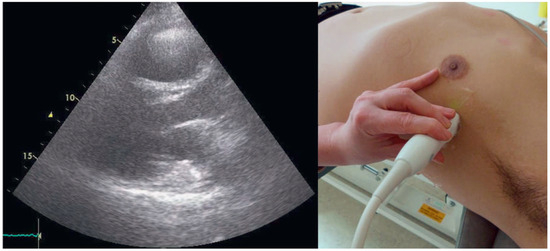

When Apical Is Parasternal, Or "Where Is the Heart?"

by Thilo Burkard and Beat A. Kaufmann

Cardiovasc. Med. 2015, 18(7-8), 226; https://doi.org/10.4414/cvm.2015.00345 - 12 Aug 2015

Viewed by 147

Abstract

A 57-year-old male presented to the medical outpatient department with typical angina pectoris Canadian Cardiovascular Society (CCS) class II and dyspnoea on exertion during the previous weeks [...] Full article

Show Figures

Figure 1